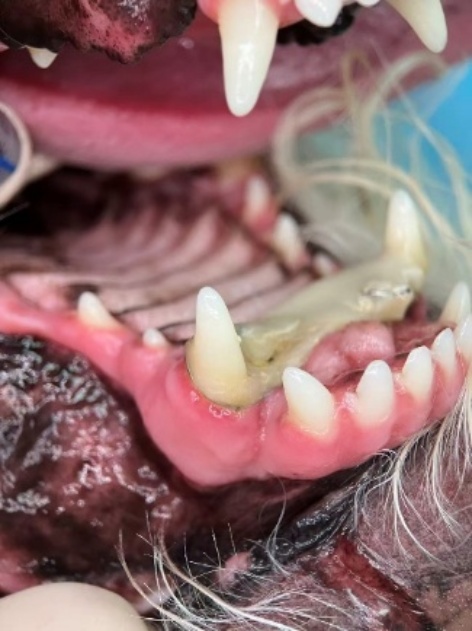

口腔检查见左上犬齿(204)明显向唇侧偏移约1 cm,牙龈撕裂并伴少量出血(图1)。探诊无明显牙冠裂纹或崩损,牙齿未见明显变色。结合病史,诊断为犬齿外伤性侧向脱位伴牙槽骨裂。经过细致且全面的沟通后,宠主意向选择固定术保留患齿,并知悉全部操作流程及可能存在的并发症。

Figure 1. Preoperative appearance of lateral luxation of the tooth in the affected dog

1. 患犬术前牙齿侧向脱位外观